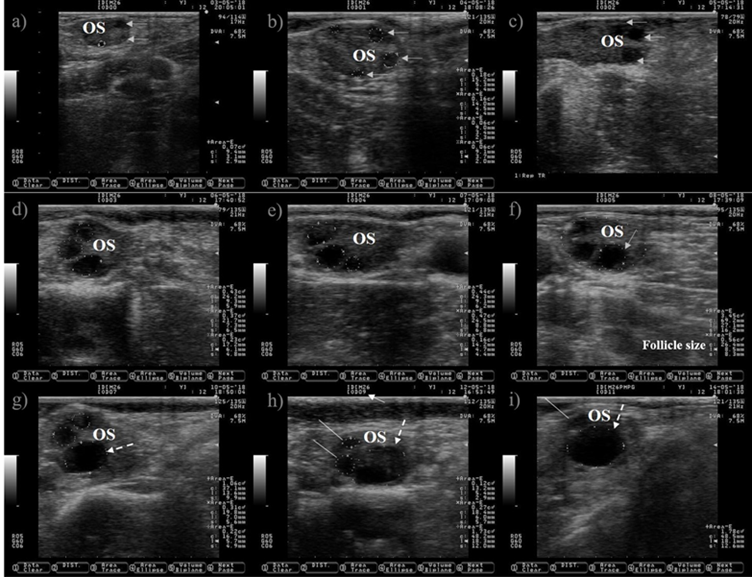

Ultrasound allows to visualize only the selection and dominance phase of the follicular wave, but not the recruitment phase because it takes place at very early stage of follicular development. The preovulatory follicle at day zero and the subsequent corpus luteum were located in the left ovary, but only pictures of the right ovary are shown because is where the follicle wave emerged. a) a small antral follicle is encircled with a dotted line at day zero (the anechogenic characteristics of the follicular fluid makes the follicle appears as dark circle), gray arrows are indicating the presence of other two antral follicles. b) the follicle wave has emerged, the four follicles are encircled with dotted lines at day one, three of them were previously observed at day zero (gray arrows). c) the gray arrows are pointing to the three follicles observed since day one, the increase in its size is easily observed at day two. The growth of the three follicles (dotted lines) observed since day zero is depicted in Pictures c) and d) (day three and four). e) the dominant follicle of the follicular wave is selected (selection of the dominant follicle occurs when the largest follicle reaches approximately 8.5 mm in diameter11), this marks the end of the selection and the commencement of the dominance phase. The growth of the dominant follicle (dashed arrows) and the atresia of the subordinate follicles (white lines) are depicted in Pictures g) to i). OS: ovary stroma. White arrow: day of the estrous cycle. Pictures were taken using a 7.5 MHz probe.

Figure 1 Pictures depicting follicle wave growth in dairy cattle from estrus (day 0) to day 11 of the estrous cycle

The ovarian follicles grow in cyclic and organized events known as follicular waves (Figure 1). A follicular wave comprises three fixed (recruitment, selection and dominance) and two conditional (atresia or ovulation) stages8. During the fixed stages a dominant follicle is selected from a cohort of growing follicles, while the unselected (subordinate) follicles suffer atresia. A growing follicle must have access to IGF-I, express LH receptors and synthesize estradiol under low FSH concentrations conditions in order to reach the stage of dominance9. After dominance, the selected follicle will undergo atresia or ovulation depending on the hormonal environment. Ovulation will occur if the follicle reaches the dominance stage under declining blood progesterone concentrations, otherwise it will suffer atresia and a new wave will emerge. Follicle wave emerging is characterized by the appearance of several follicles between 3-4 mm10. Two or three waves are commonly observed during the estrous cycle in cattle11.